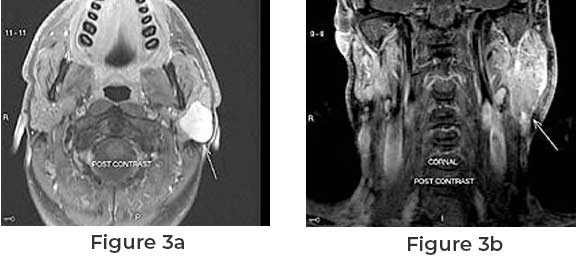

Parotid tumors are not very common; you may require extra care, and it also may lead to surgery in case of the infectious Parotid tumor. But if you have gone through the Parotid tumor surgery then on the first day after the surgery firstly the drain tube will be removed. The second day of the surgery is all about parotid dressing removal. After the removal of the parotid dressing the area of surgery must be open so that air could pass which lead to a quick recovery.